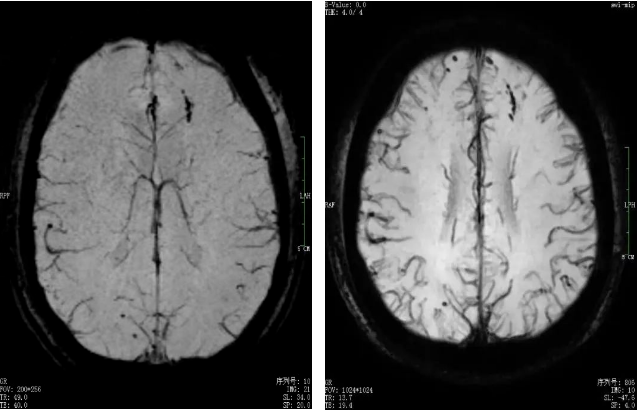

1.5T(左)3.0T(右)头颅磁敏感对比